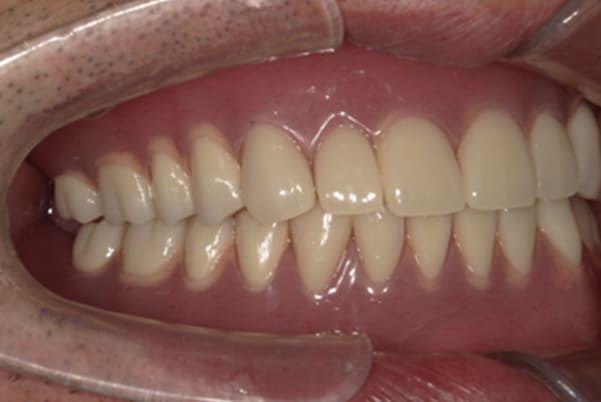

症例レポート[CASE.02]

- 男性(60代)

- 入れ歯がカパカパする、歯がぐらぐらして痛い、食いしばれない

- 治療

- 上顎精密総金属床総入れ歯

- 下顎精密金属床部分入れ歯

- ジルコニアクラウン4歯

- 治療期間

- 約3か月間

- 費用

- 上顎精密総金属床総入れ歯:55万円

- 下顎精密金属床部分入れ歯:55万円

(ミリング、ラベット加工込み) - ジルコニアクラウン:11万円×4歯

合計:154万円(税込)

上の前歯が重度歯周病により動揺し、残せない状態のため、入れ歯も動揺がありました。

ご自身の歯に負担の少ないバネ、また見た目も改善

銀歯からセラミック歯に

バネをかける歯は繋げることで強度を増し、歯への負担を軽減し、歯の寿命を長くする設計へ。

バネがかかる歯の被せ物は、歯への負担を減らし、入れ歯が動きにくいようになる形態をあらかじめ付与することで、より入れ歯の機能が高まります。

治療を行う際、被せ物や入れ歯は、別々に考えるのではなく、一口腔単位としてお口全体のことを考え最良の治療計画を立てることが歯の寿命、機能効果を向上させるため、専門医としてこのことは常に心掛けて治療を行っています。

治療前は上下奥歯の入れ歯が削れていることで、かみ合わせが低くなり唇もつむった状態でした。

かみ合わせを適切な高さに戻したことで、本来の自然な口元へ。